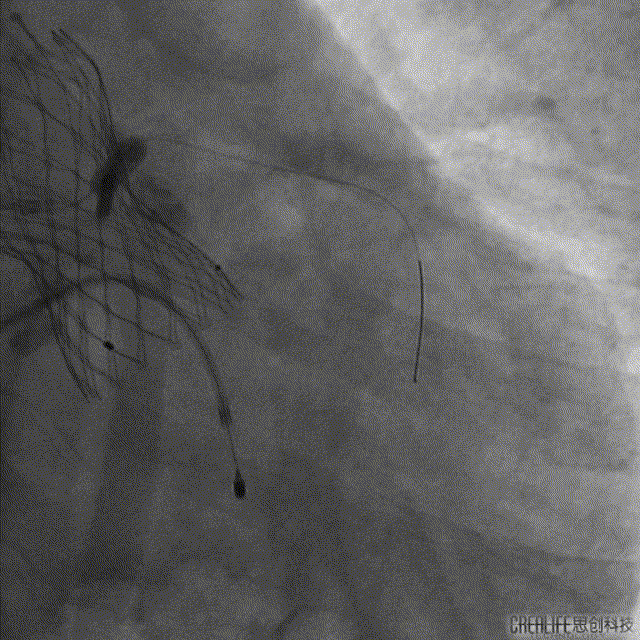

主动脉根部造影